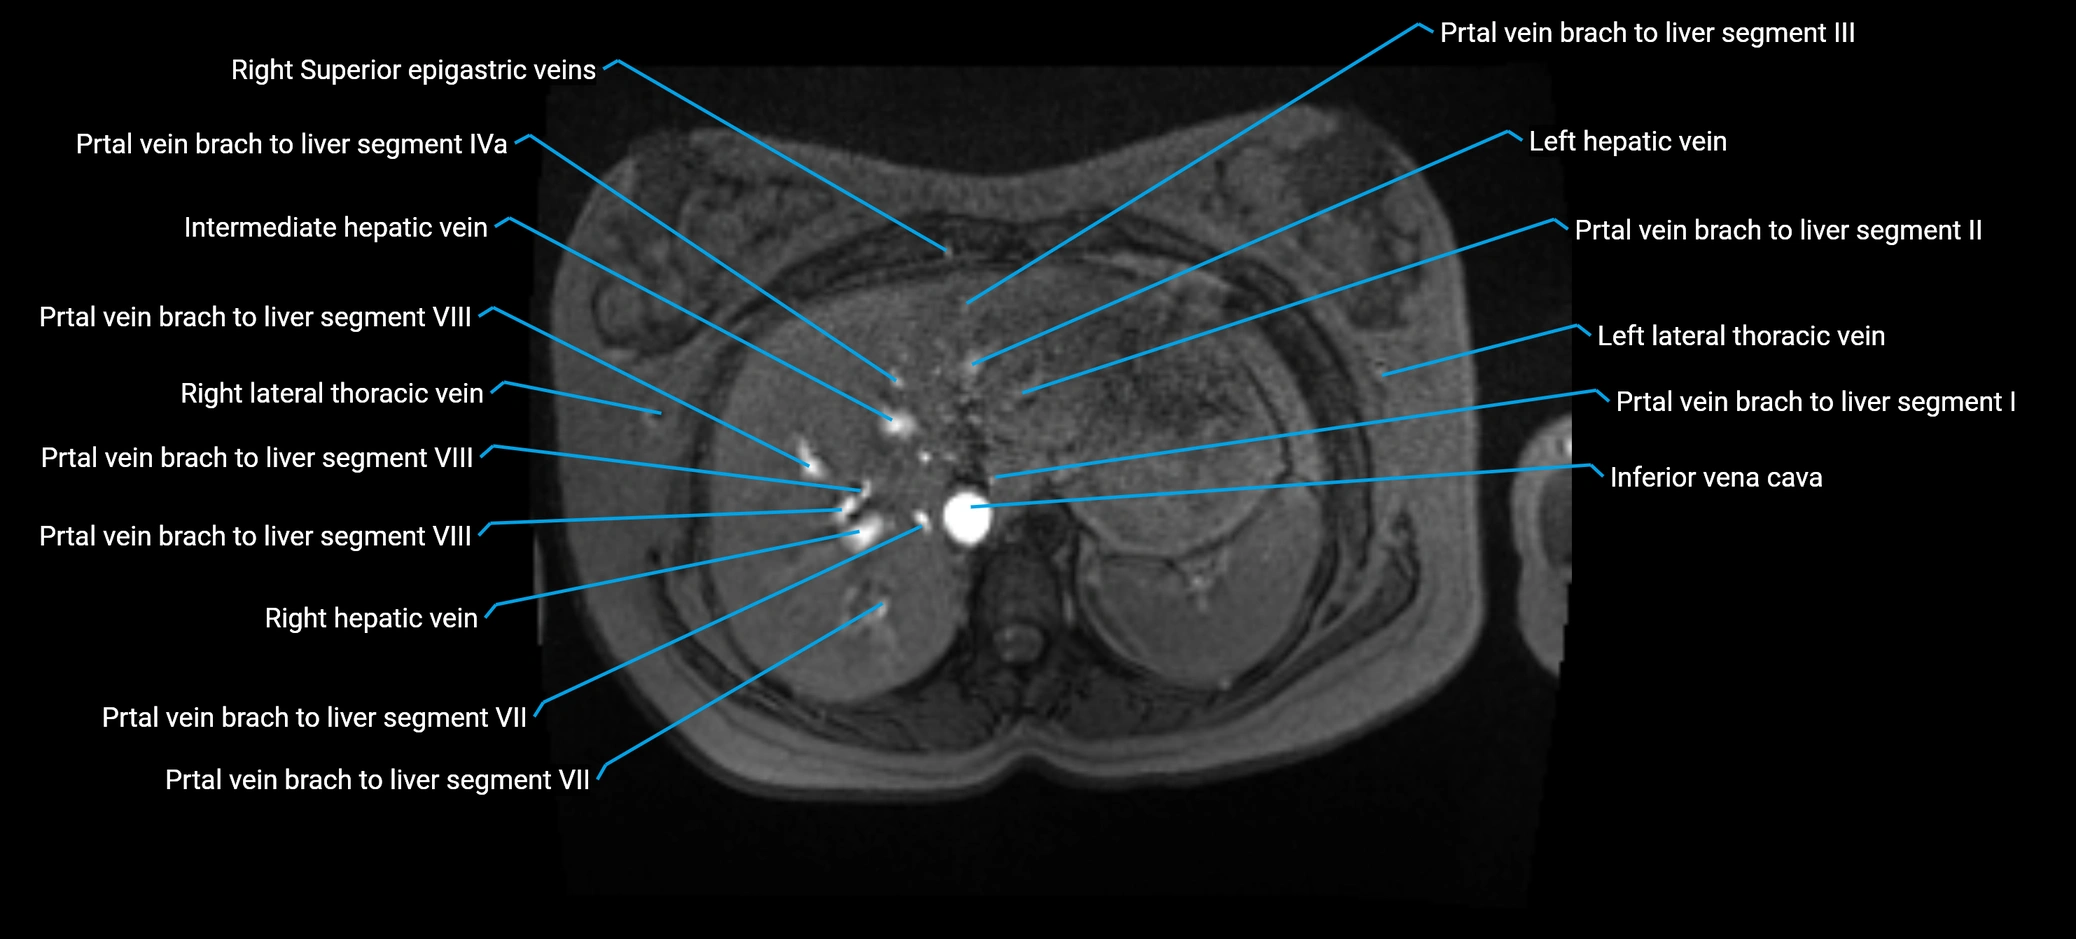

MRI image

image